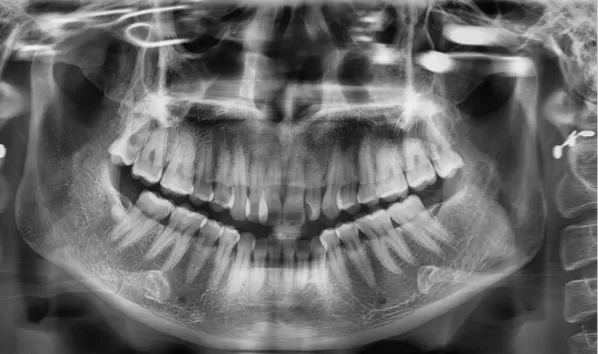

Rayons X avant le traitement

[Radiographie panoramique/Céphalogramme latéral]